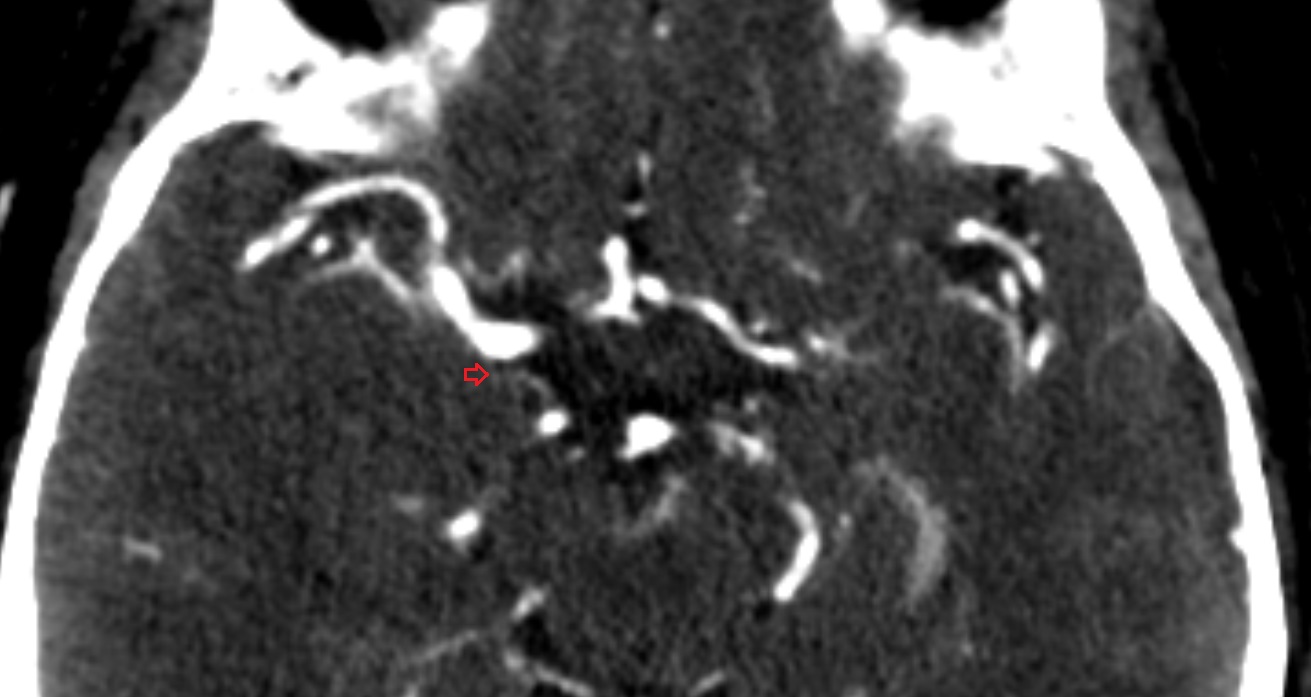

- Cerebellopontine cistern